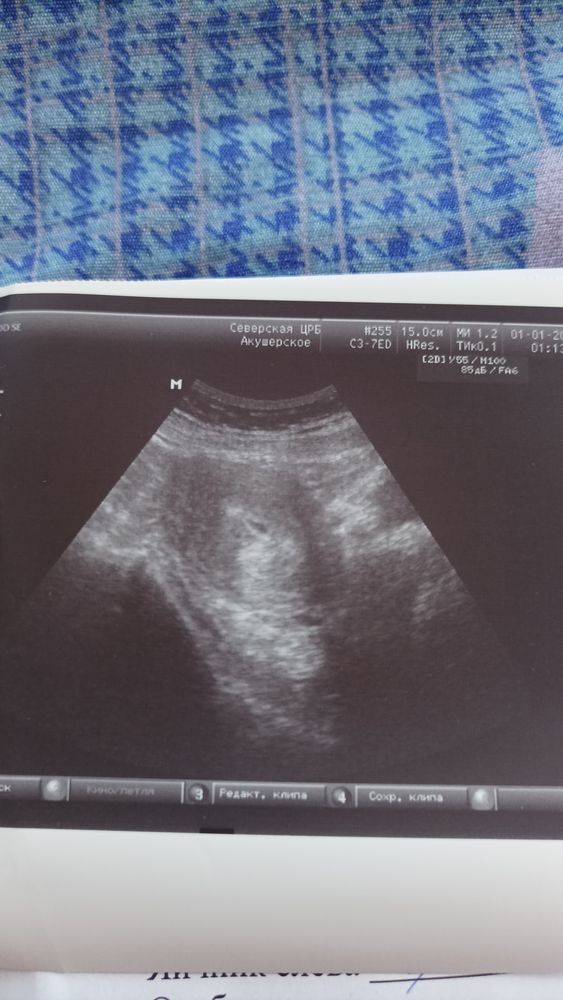

Девочки может было у кого так и всё кончилось благополучно, я сегодня пошла на УЗИ срок 5.4 чтобы проверить что всё на месте,плодное яйцо увидели но узистка сказала что может быть замершая потому что деформировано оно, но есть шанс что выпрямится, контроль через неделю, у меня до этого беременность тоже была замершая ,очень боюсь повторения, к врачу только 2 августа. Есть шанс что всё будет хорошо?